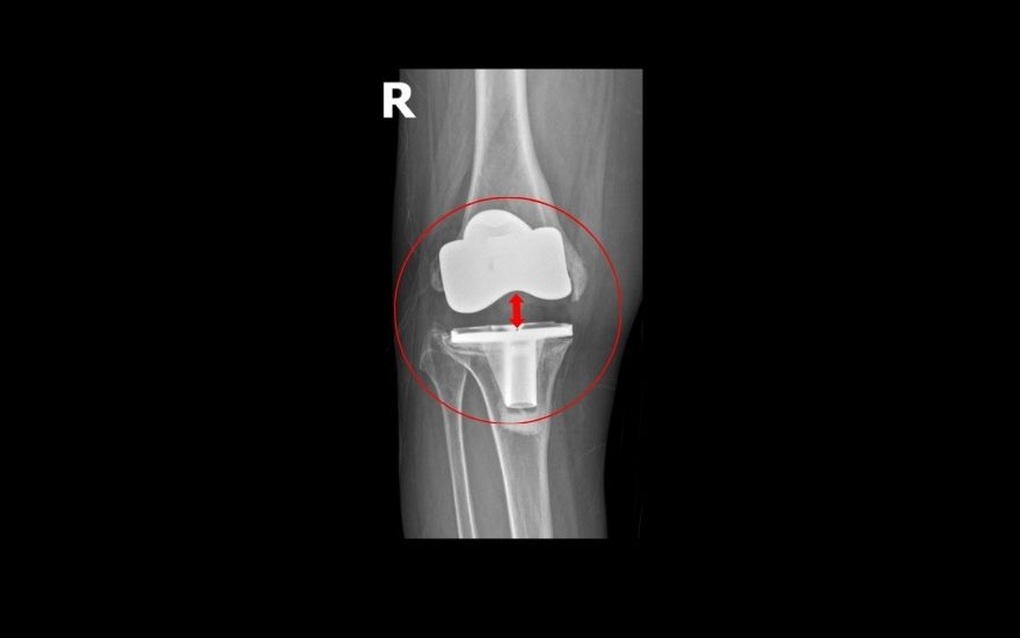

Khớp gối nhân tạo lỏng lẻo, di lệch khỏi ổ khớp (Ảnh: BVCC).

TS.BS Lê Quang Huy, Trưởng khoa Ngoại Chấn thương chỉnh hình – Thần kinh sọ não, BVĐK Hồng Ngọc – Phúc Trường Minh cho biết trường hợp của bà Oanh rất hiếm gặp. Sau gần 5 năm phẫu thuật, khớp gối nhân tạo di lệch và lún sâu vào đầu xương đùi khoảng 2 cm, gây ra tình trạng mất vững, mất cân bằng mô mềm quanh khớp dẫn đến bệnh nhân không đi lại được.